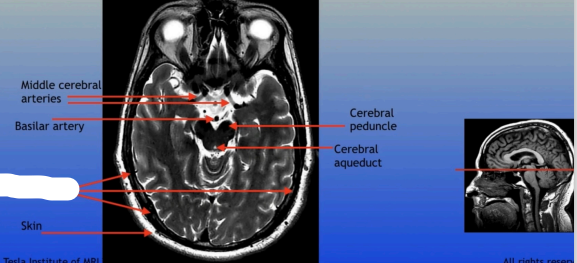

Middle Cerebral Arteries

Basilar Artery

Skin

Cerebral Peduncle

Cerebral Aqueduct